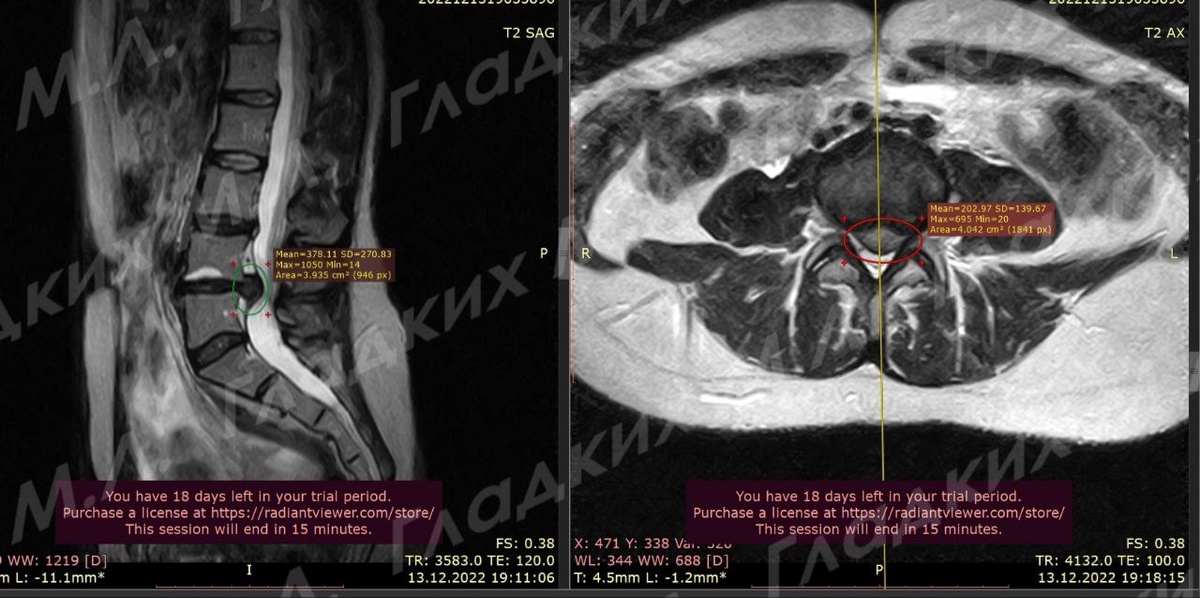

По МРТ была диагносци отрована грыжа в пояснице на уровне L4-L5 ( первое фото).

На МРТ через 3 месяца вы видите что грыжа светлая ( второе фото). Это нормальная реакция организма, иммунные клетки которого сначала «размягчают» грыжу, а потом убирают ее.